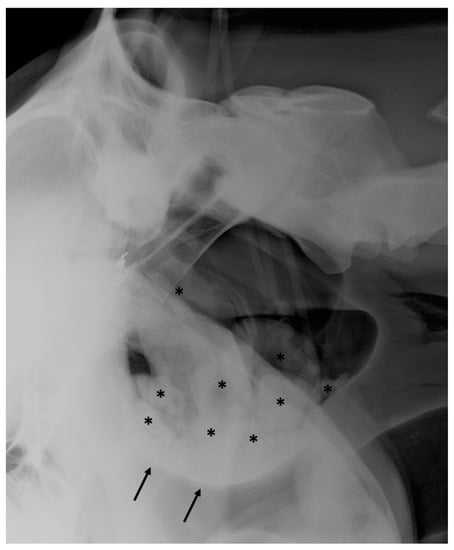

3.3. Guttural Pouch Hemorrhage